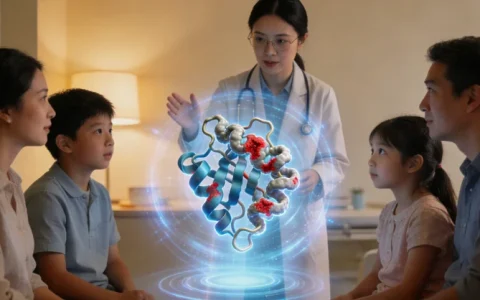

流程其实比想象中简单、私密。第一步,也是最重要的一步,是专业的遗传咨询。这不是简单的开单检查,而是一次深入的交谈。咨询专家会详细了解至少三代的家族疾病史,绘制家系图,评估检测的必要性和意义,并充分告知可能的结果及带来的心理、家庭影响。之后,如果决定检测,通常只需抽取一小管静脉血,或者用口腔拭子在口腔内壁轻轻刮取细胞样本即可。样本会由专业的冷链物流送至具备资质的实验室。整个采样过程在本地医院或合作采样点就能完成,非常便捷。目前,昌吉地区已有像 万核基因 这样的专业检测机构,能够提供从前期咨询、样本采集到报告解读、后续健康管理建议的一站式服务,让边疆地区的居民也能享受到一线城市的精准医疗资源。

让我想起去年接触的一位来自昌吉周边渔业的劳动者,刘女士,38岁。她的父亲和姑姑都因结肠癌去世,哥哥也常年受息肉困扰。作为家里主要的劳动力之一,她常年在水上劳作,饮食不规律,心里一直压着这块大石头,既怕自己生病,更怕耽误了正在上初中的女儿。在反复咨询后,她鼓起勇气带着哥哥的病史资料,为自己和女儿做了AFAP基因检测。结果证实,她携带了家族性的APC基因突变,而她的女儿是幸运的,并未遗传。这个结果,对刘女士一家是转折点。对于刘女士自己,她不再活在模糊的恐惧中,而是立刻制定了严格的肠镜监测计划,并在生活中进行调整。而知道女儿没有遗传这个风险,是她最大的慰藉,让她能更安心地工作,为女儿规划一个无忧的未来。这个案例清楚地告诉我们,基因检测带来的不仅是风险警示,更是对健康生活的精准指导和对家人未来的确定性保障。

这是非常务实的问题。基因检测不是终点,而是精准健康管理的起点。如果检测结果为阳性,核心后续管理就是建立规律的结肠镜监测计划。昌吉州及乌鲁木齐的三甲医院消化内科完全具备开展高质量肠镜检查及息肉镜下治疗的能力。检测机构提供的报告和遗传咨询意见,将成为您与本地消化科医生沟通的“桥梁”,帮助医生为您制定最个体化的筛查频率和方案。整个管理过程,是基因检测机构与本地医疗资源的有效协作。